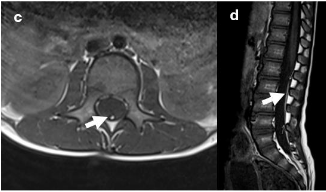

The data analyzed included gender, age at the time of surgery, and preoperative symptoms related to TCS. These symptoms encompassed motor function disturbances: degree of paresis, gait ataxia, ambulation ability, and results from neurophysiological tests such as somatosensory evoked potentials (SEPs) and, if performed, motor evoked potentials (MEPs), bladder function (urodynamic findings including bladder capacity, compliance, post-void residual volume, frequency of urination, catheterization frequency if applicable, incidence of urinary tract infections, and presence of urge or stress incontinence), bowel function, back pain, as well as the type and severity of foot or spinal deformities. Additionally, the presence of associated developmental disorders or genetic alterations. Each diagnosis was confirmed through lumbar magnetic resonance imaging (MRI) in conjunction with clinical and electrophysiological findings (exemplary illustration is provided in figure 1A and 1B).

Figure 1A. Syringomyelia in a T2-weighted lumbar MRI

T2-weighted axial (a) and sagittal (b) MR image demonstrating a pointed conus medullaris with associated syringomyelia (arrows) with a maximum diameter of 5mm. The underlying reason is a tight fatty filum (arrows), which can be seen in the corresponding T1-weighted axial (c) as well as sagittal (d) MR images.

Figure 1B. Tight fatty filum in a T1-weighted lumbar MRI